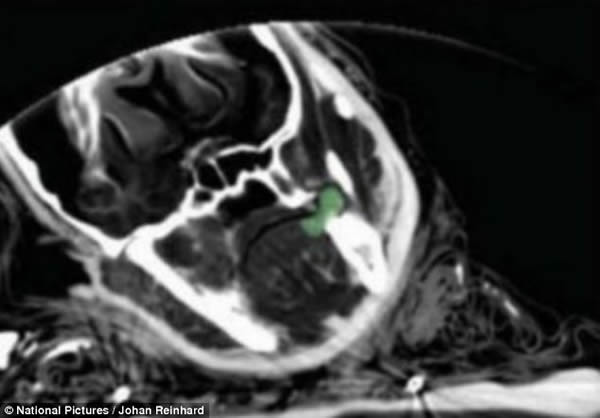

嘴巴内部轴向X光照片显示牙齿之间的古柯叶(绿色部分)。古柯叶和酒精是引发交替状态的物质,这被认为是神圣的,它向受害人以及与受害人相关的人们暗示着神的亲近。

少女的头骨(黄色)、牙齿(橙色)、舌头(红色)和古柯叶(绿色)的3D可视化。少女嘴里还有残余了几片古柯叶。